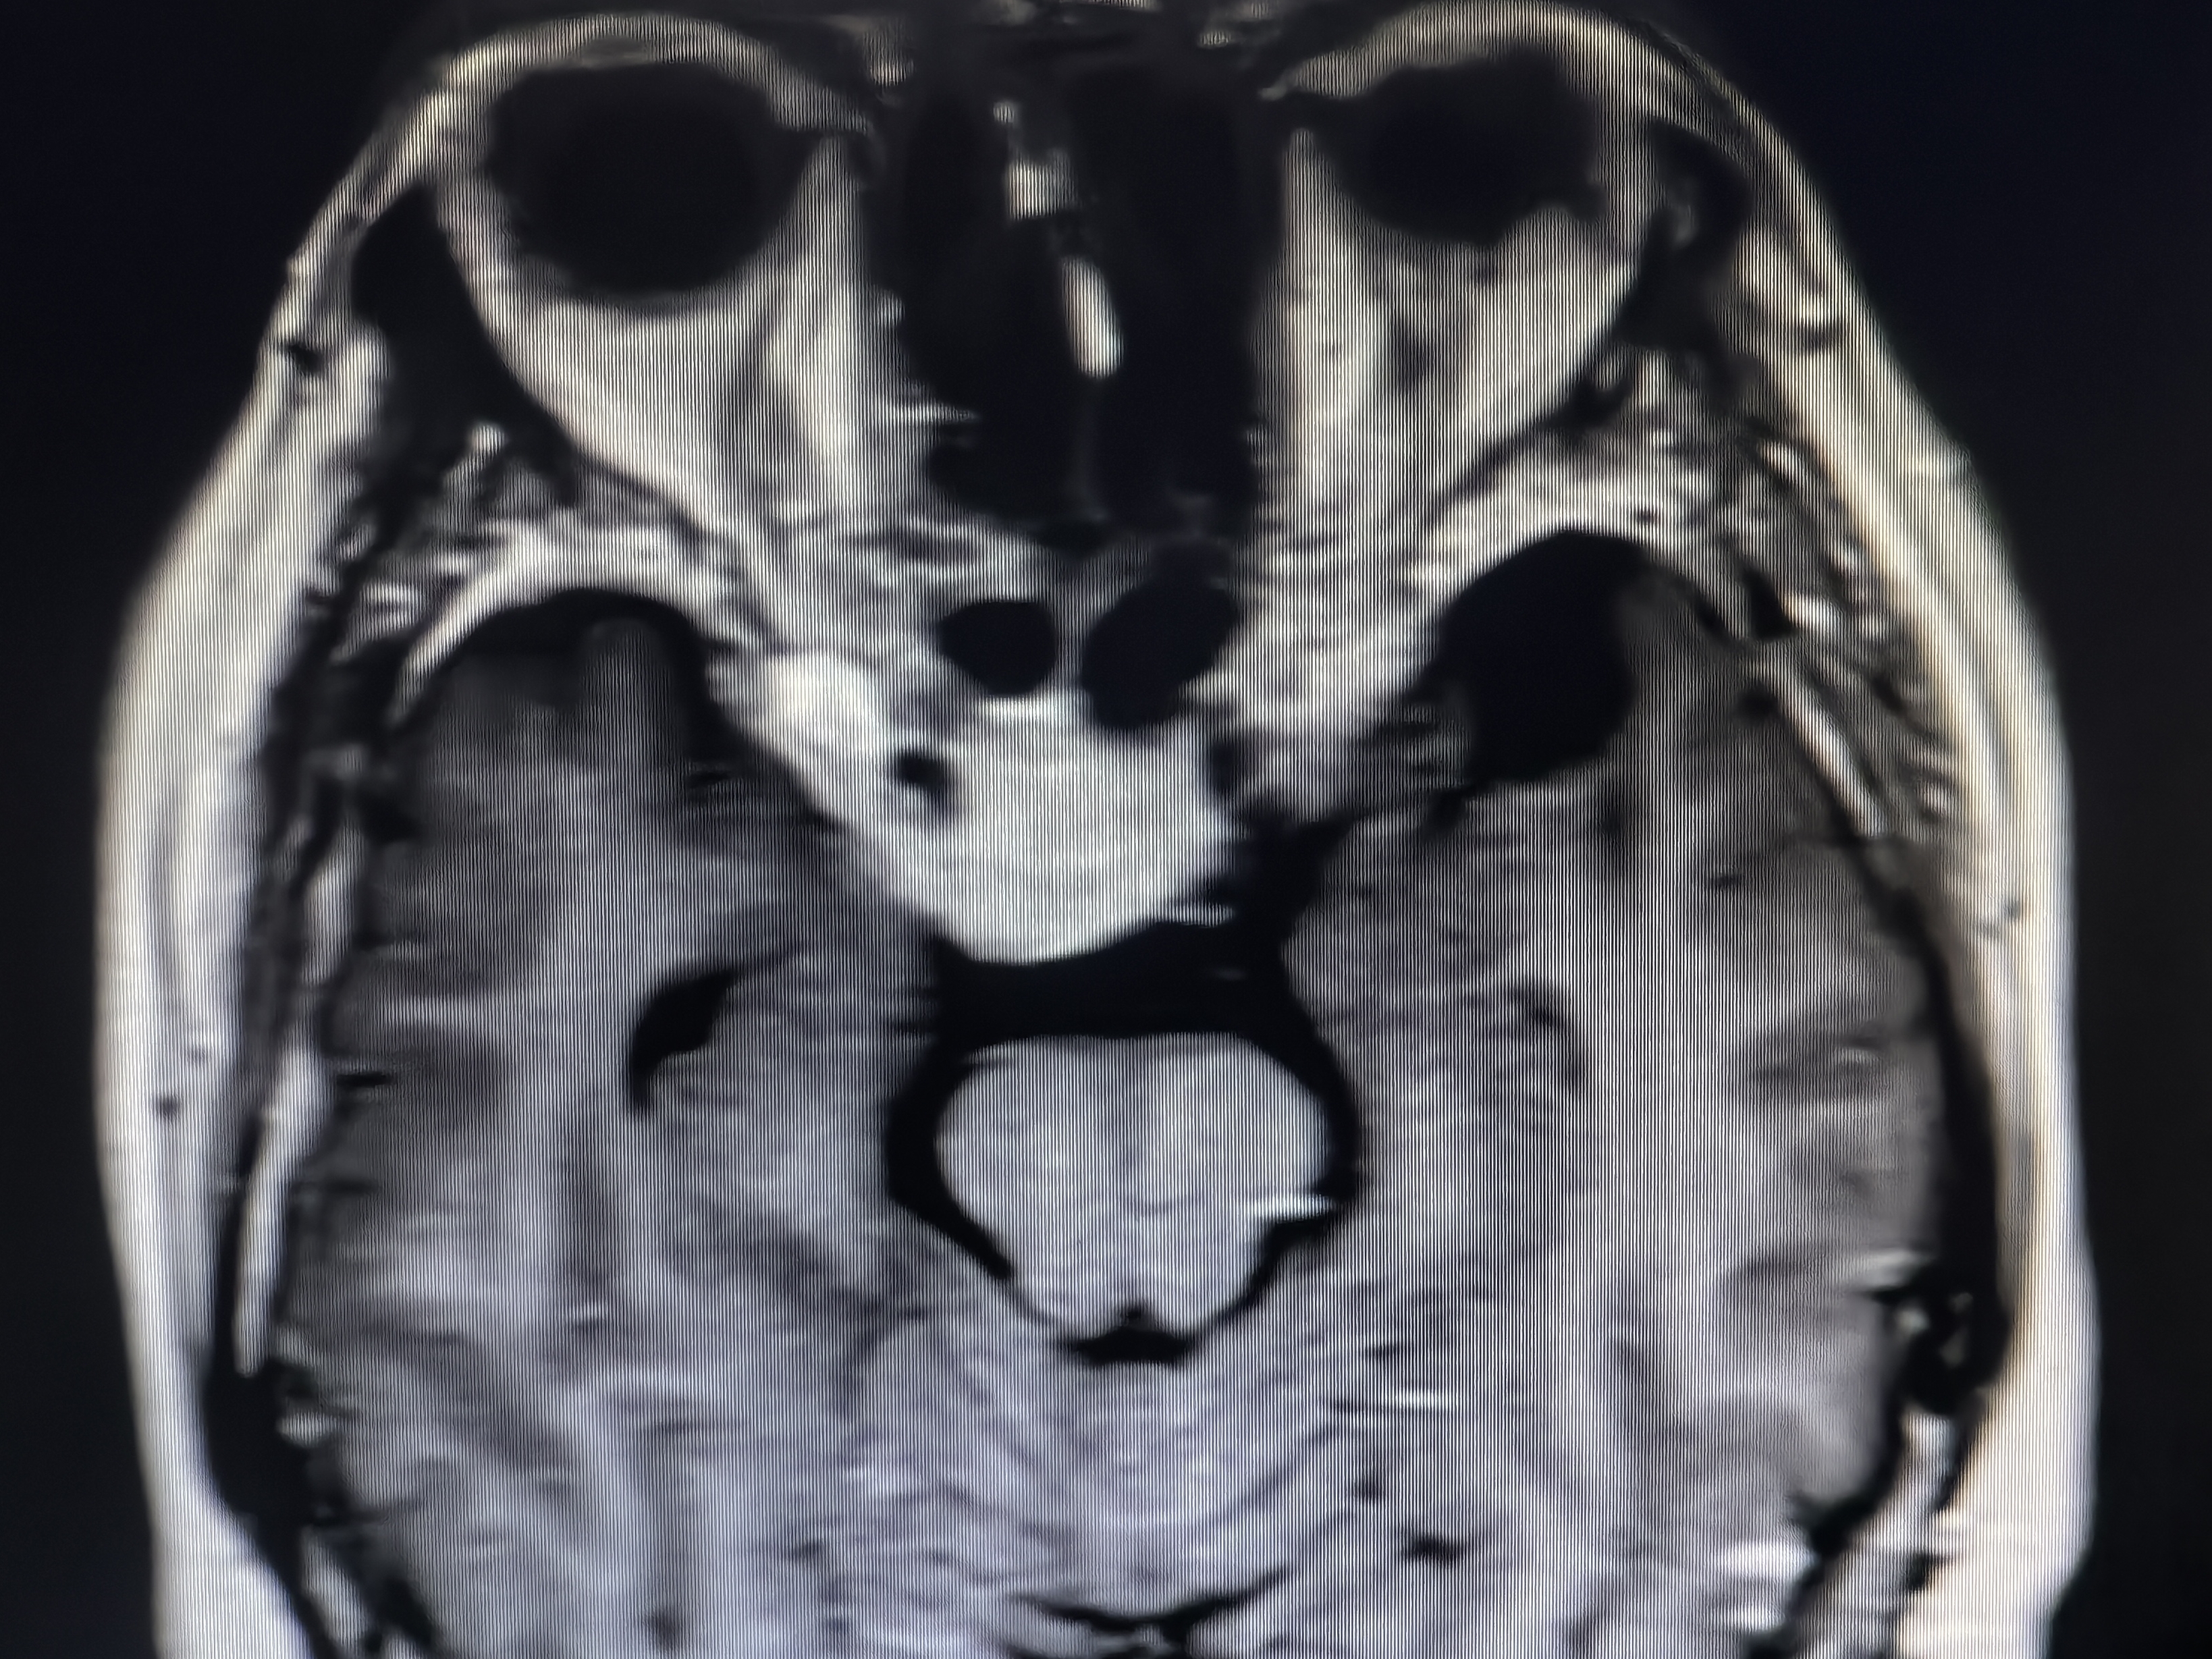

下面展示本病房几例病例:

病例三